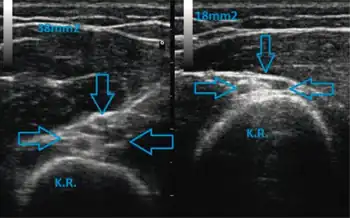

Radial nerve neurapraxia arrows resulting from the compression of the nerve at the level of the spiral groove